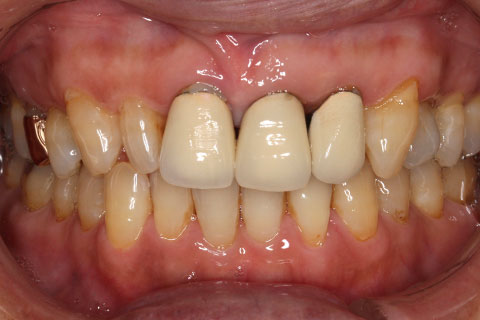

オールセラミックの症例1

上顎前歯のデコボコと色調を改善。

- 年齢・性別

- 40歳女性

- 治療期間

- 1ヶ月

- 抜歯

- なし

- 治療費

- 35.2万円

- 備考

- 前歯4本の変色歯及び歯列不正によるセラミック治療

- 治療内容

- 歯質を削除し、セラミック冠をセメント合着

- 施術の副作用(リスク)

- 知覚過敏、歯髄炎、荷重負担